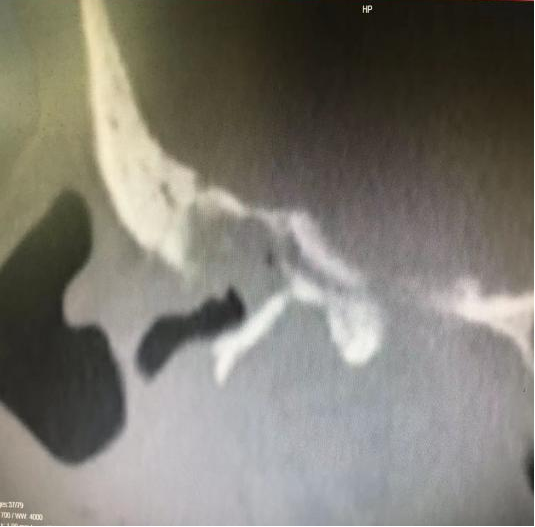

▲右侧外耳道后上壁破坏;右侧外半规管及面神经水平段骨质破坏

诊断:1.右侧中耳胆脂瘤。2.右侧极重度感音神经性耳聋。3.右侧周围性面神经面瘫(house 4级)。

完善专科检查,排除手术禁忌后,术前充分沟通后行全麻手术,术中发现乳突、鼓窦、上鼓室大量肉芽及胆脂瘤样物,听小骨中锤骨、砧骨已破坏、吸收,清理镫骨周边肉芽及胆脂瘤上皮,水平段面神经被肉芽组织及胆脂瘤包裹,清理肉芽组织及胆脂瘤上皮后,发现面神经水平段骨质缺损2mm左右,鞘膜水肿。在顾问医生吴旋教授指导下,主刀医生陈君主任顺利完成显微镜下右耳镫骨黏连松解术+改良乳突根治术+面神经松解减压术+外耳道成形术,彻底切除乳突、中耳胆脂瘤病灶,术后面瘫明显改善。术后1月患者返院复查,术腔已干耳。